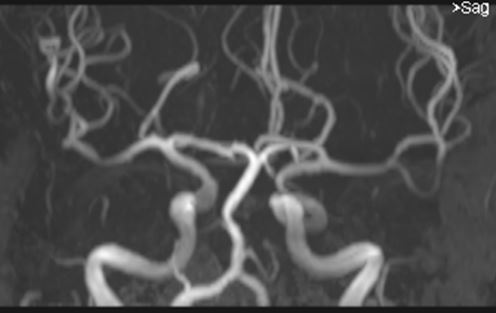

Article: Standardized assessment of the signal intensity increase on unenhanced T1-weighted images in the brain: the European Gadolinium Retention Evaluation Consortium (GREC) Task Force position statement

Authors: Carlo C. Quattrocchi, Joana Ramalho, Aart J. van der Molen, Àlex Rovira, Alexander Radbruch & on behalf of the GREC, European Gadolinium Retention Evaluation Consortium and the European Society of Neuroradiology